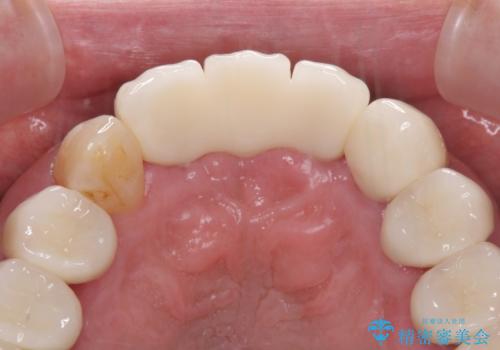

上の歯は見た目を良くしたいというご希望があったため、歯周外科処置を行った歯についてはセラミッククラウンで補綴することとしました。

気になっていた歯の痛みや歯肉からの出血がなくなり、改善したいと思っていた外見も綺麗に仕上がり、大変満足していただきました。